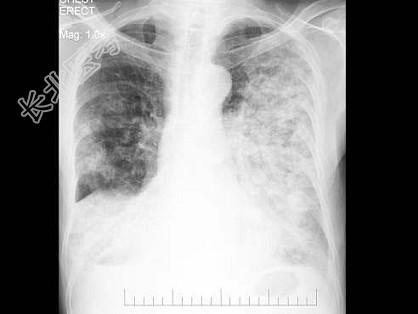

- 单项选择题男,56岁, 痰中带血1月余,X线检查如图, 最可能的诊断是 ( )

A、两肺炎症

B、肺转移瘤

C、血行播散型肺结核

D、细支气管肺泡癌

E、矽肺